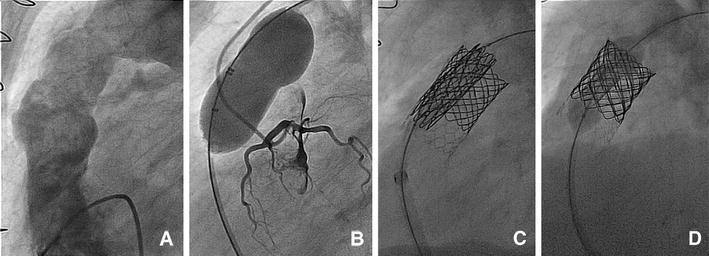

First implantation of the CE-marked transcatheter Sapien pulmonic valve in Europe.

Clin Res Cardiol. 2011 Jan;100(1):85-7. doi: 10.1007/s00392-010-0214-y. Epub 2010 Sep 18.

DOI:10.1007/s00392-010-0214-y

PMID:20852873

原文链接:https://pmc.ncbi.nlm.nih.gov/articles/PMC3022147/